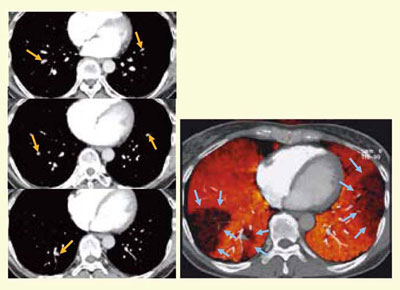

肺野領域におけるDEイメージングは,ヨード,空気,軟部組織の3点を基準としたThree-material decompositionで行う。ヨード造影剤のCT値から肺野内のヨード分布を表示する画像を作成し,CT angiography(CTA)の元画像と重ね合わせて評価する。DEイメージングでは,80kVと140kVの合成画像(アキシャル,コロナル,CTA)で血栓を評価し,上記のフュージョンイメージ,LungPBV像などで血流を確認し,CT venographyで静脈血栓の診断を行う(図1)。

図1 DEイメージングによる肺血栓塞栓症の評価

一方で,CTPAでは末梢の亜区域枝以下の塞栓の評価は判断が難しいことがあるが,LungPBVは塞栓部分に肺血流シンチグラフィと一致するような欠損像を示し,併用することで診断能の向上に貢献すると考えられる(図2)。

図2 LungPBVを用いた急性肺血栓塞栓症の診断

Thiemeらは2008年にEJR誌で,肺血流シンチグラムをゴールドスタンダードとして,LungPBVの良好な診断能を報告している。しかしながら,LungPBVでは,肺動脈内に血栓があっても完全閉塞でない場合や(図3),完全閉塞例でも気管支動脈などの側副血行路が発達している場合には欠損として描出されないことも少なからずあり,読影の際には注意が必要である。

| 図3 両下葉の肺血栓塞栓症のCTPAとLungPBV CTPA(左)で両下葉に血栓が認められるが,LungPBV(右)では右下葉には欠損が描出されていない。 |